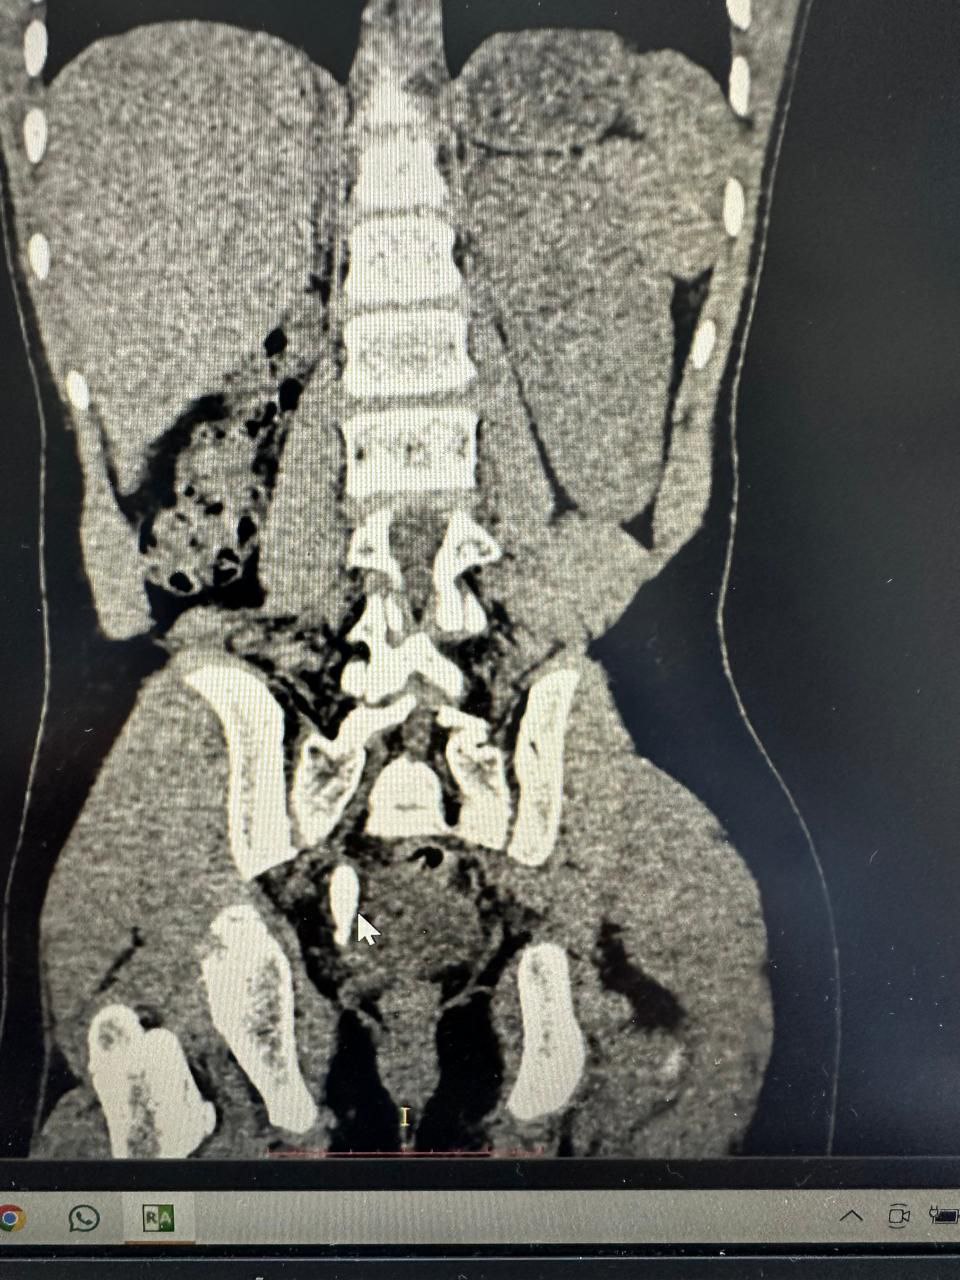

تمكن طبيب عراقي يعمل في مستشفى سفير الامام الحسين (عليه السلام) الجراحي من انقاذ مريض من عملية رفع احدى كليتيه أو إجراء أي تدخل جراحي مفتوح رغم انه كان يعاني من كلية هاجرة مترافقة مع حصاة قرن الغزال، إضافة إلى حصاة حالب كبيرة بطول (25 ملم)، وهي من الحالات المعقّدة التي تتطلب دقة عالية في التشخيص والتدخل العلاجي.

وقال المدير الاداري للمستشفى المهندس "عباس عبد علي" في تصريح خص به وكالة نون الخبرية ان" مستشفى السفير الإمام سجّل إنجازا طبيا متقدما يضاف إلى رصيده في العمليات التخصصية الدقيقة، بعد نجاح احد اطبائه الجراحين وهو الدكتور "منتظر جمال" المتخصص في جراحة الكلى والمسالك البولية، في إجراء عملية نوعية لمريض يبلغ من العمر (14 عامًا)، كان يعاني من كلية هاجرة مترافقة مع حصاة قرن الغزال، إضافة إلى حصاة حالب كبيرة بطول (25 ملم)، وهي من الحالات المعقّدة التي تتطلب دقة عالية في التشخيص والتداخل الجراحي، وتمكّن الطبيب الجراح والفريق الطبي المساعد من تفتيت الحصى بالكامل باستخدام تقنية الناظور والليزر، دون اللجوء إلى رفع الكلية أو إجراء أي تدخل جراحي مفتوح، وهو ما أسهم في تقليل المضاعفات وتسريع فترة التعافي.